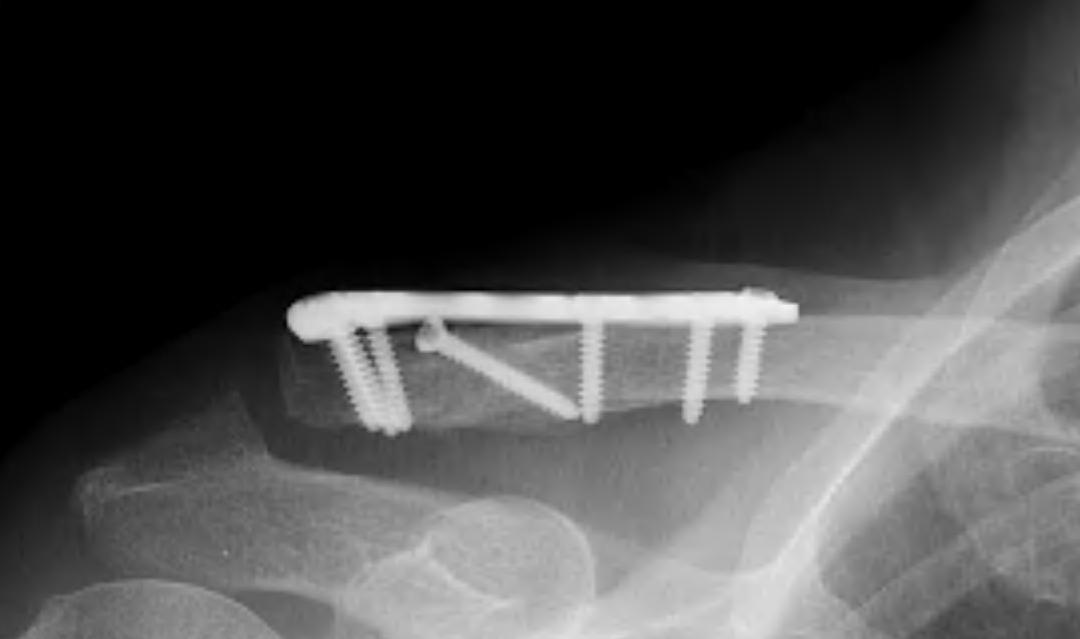

Dorsal locking plate +/- CC ligament reconstruction

Dorsal locking plate +/- CCL reconstruction

Advantage

No need to remove

Disadvantage

Lateral screws under significant tension and subsequently higher rate of screw/plate pull-out

Indication

Sufficient lateral bone to obtain fixation

Consider having hook plate available / supplement with coraco-clavicular fixation

Technique

Dorsal locking plate with cerclage fibretape

- precontoured distal locking plate in 35 patients

- all united at mean of 4 months

- excellent outcomes scores

Xu et al BMC Musculoskeletal Disorders 2019

- 16 patients with locking plate versus 18 with plate + CC suture anchors

- shorter union time (14 v 16 weeks) and better outcomes (94 v 90 Constant) with suture anchors